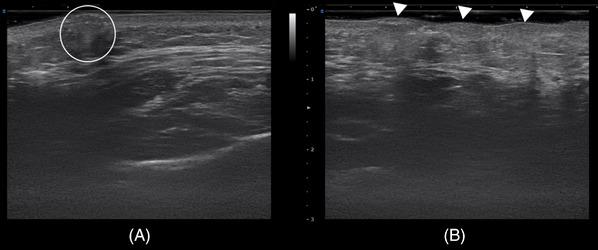

The study involved conducting intradermal injections on four cadavers and participants using a 2 mm length, 34-gauge needle (N-Finders, Inc., South Korea). During the cadaveric study, the polynucleotide prefilled syringe was dyed green, and an anatomist performed dissections, removing only the skin layer. Ultrasonographic observations were carried out to ensure accurate intradermal injection placement.

本研究使用 2 毫米长、34 号针(N-Finders,Inc.,韩国)对四名尸体和参与者进行皮内注射。在尸体研究中,多核苷酸预装注射器被染成绿色,解剖学家进行解剖,仅去除皮肤层。进行超声观察以确保准确的皮内注射位置。